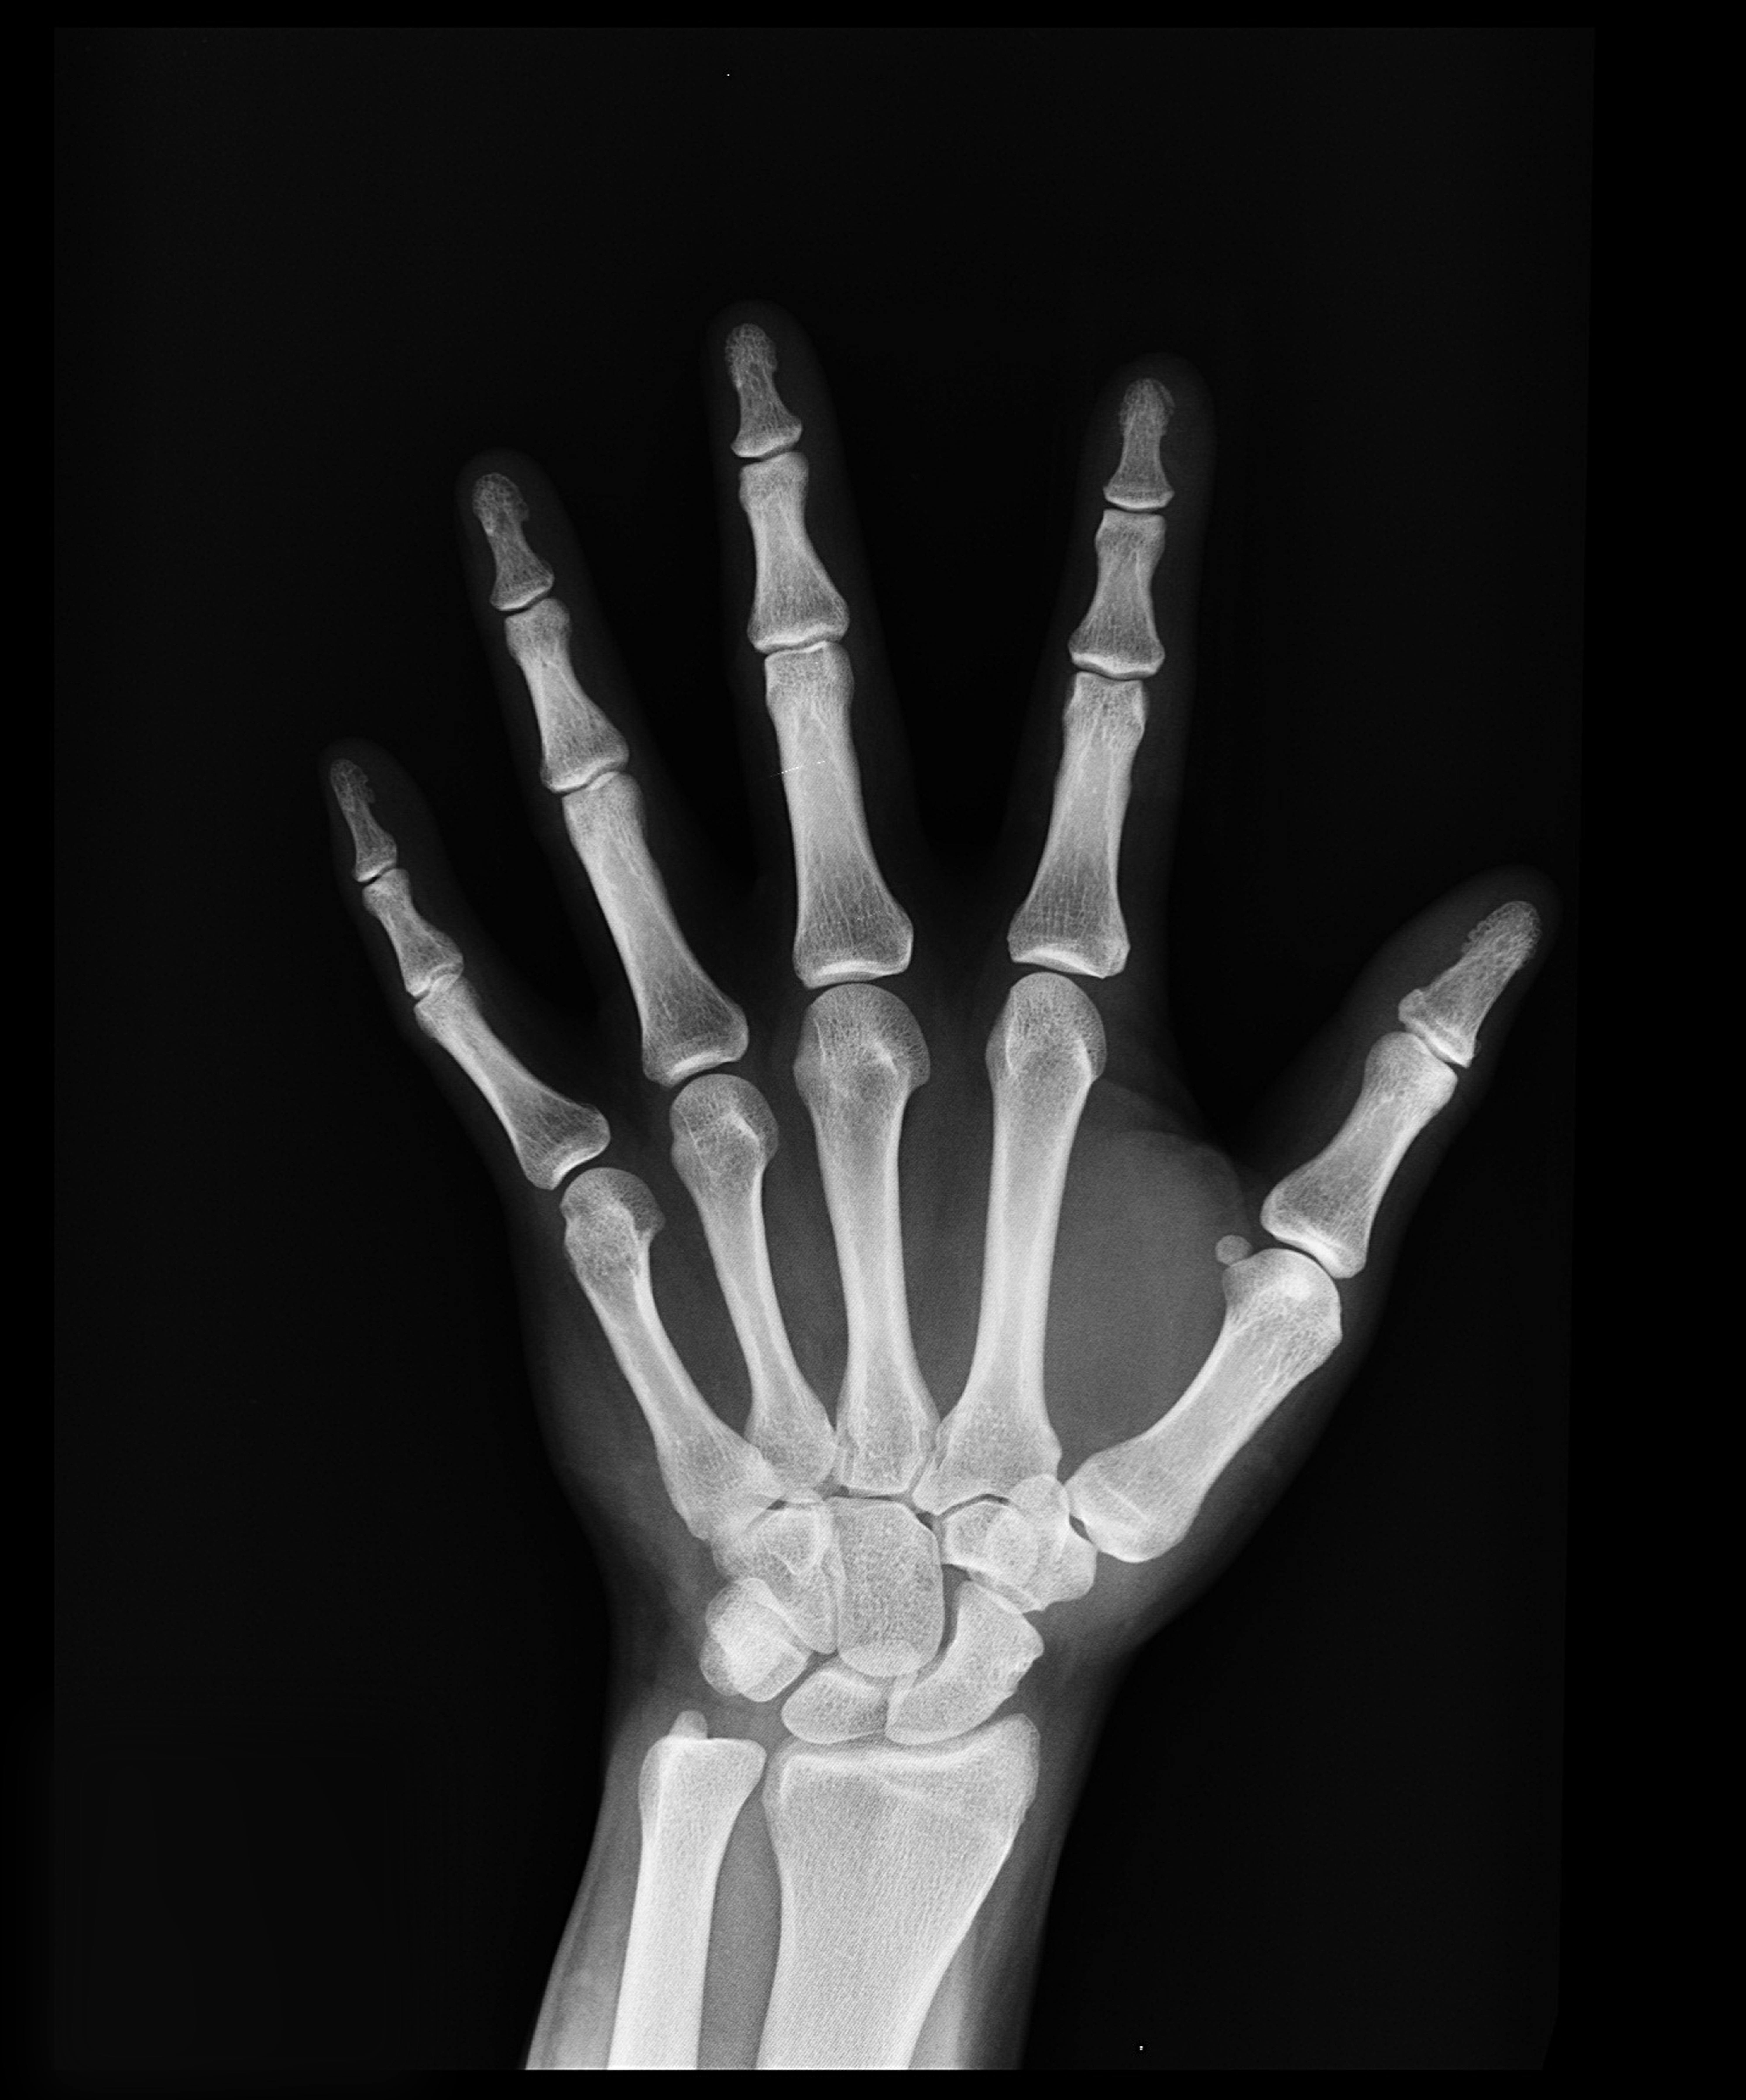

Bone Fracture Detection

Bone fracture detection using XGBoost works by preprocessing X-ray images, extracting key features, and training the model to classify fractured vs. normal bones. XGBoost combines multiple decision trees to learn patterns more accurately, allowing it to detect fractures in new images with high reliability.

Python Pandas Numpy scikit-learn XGBoost